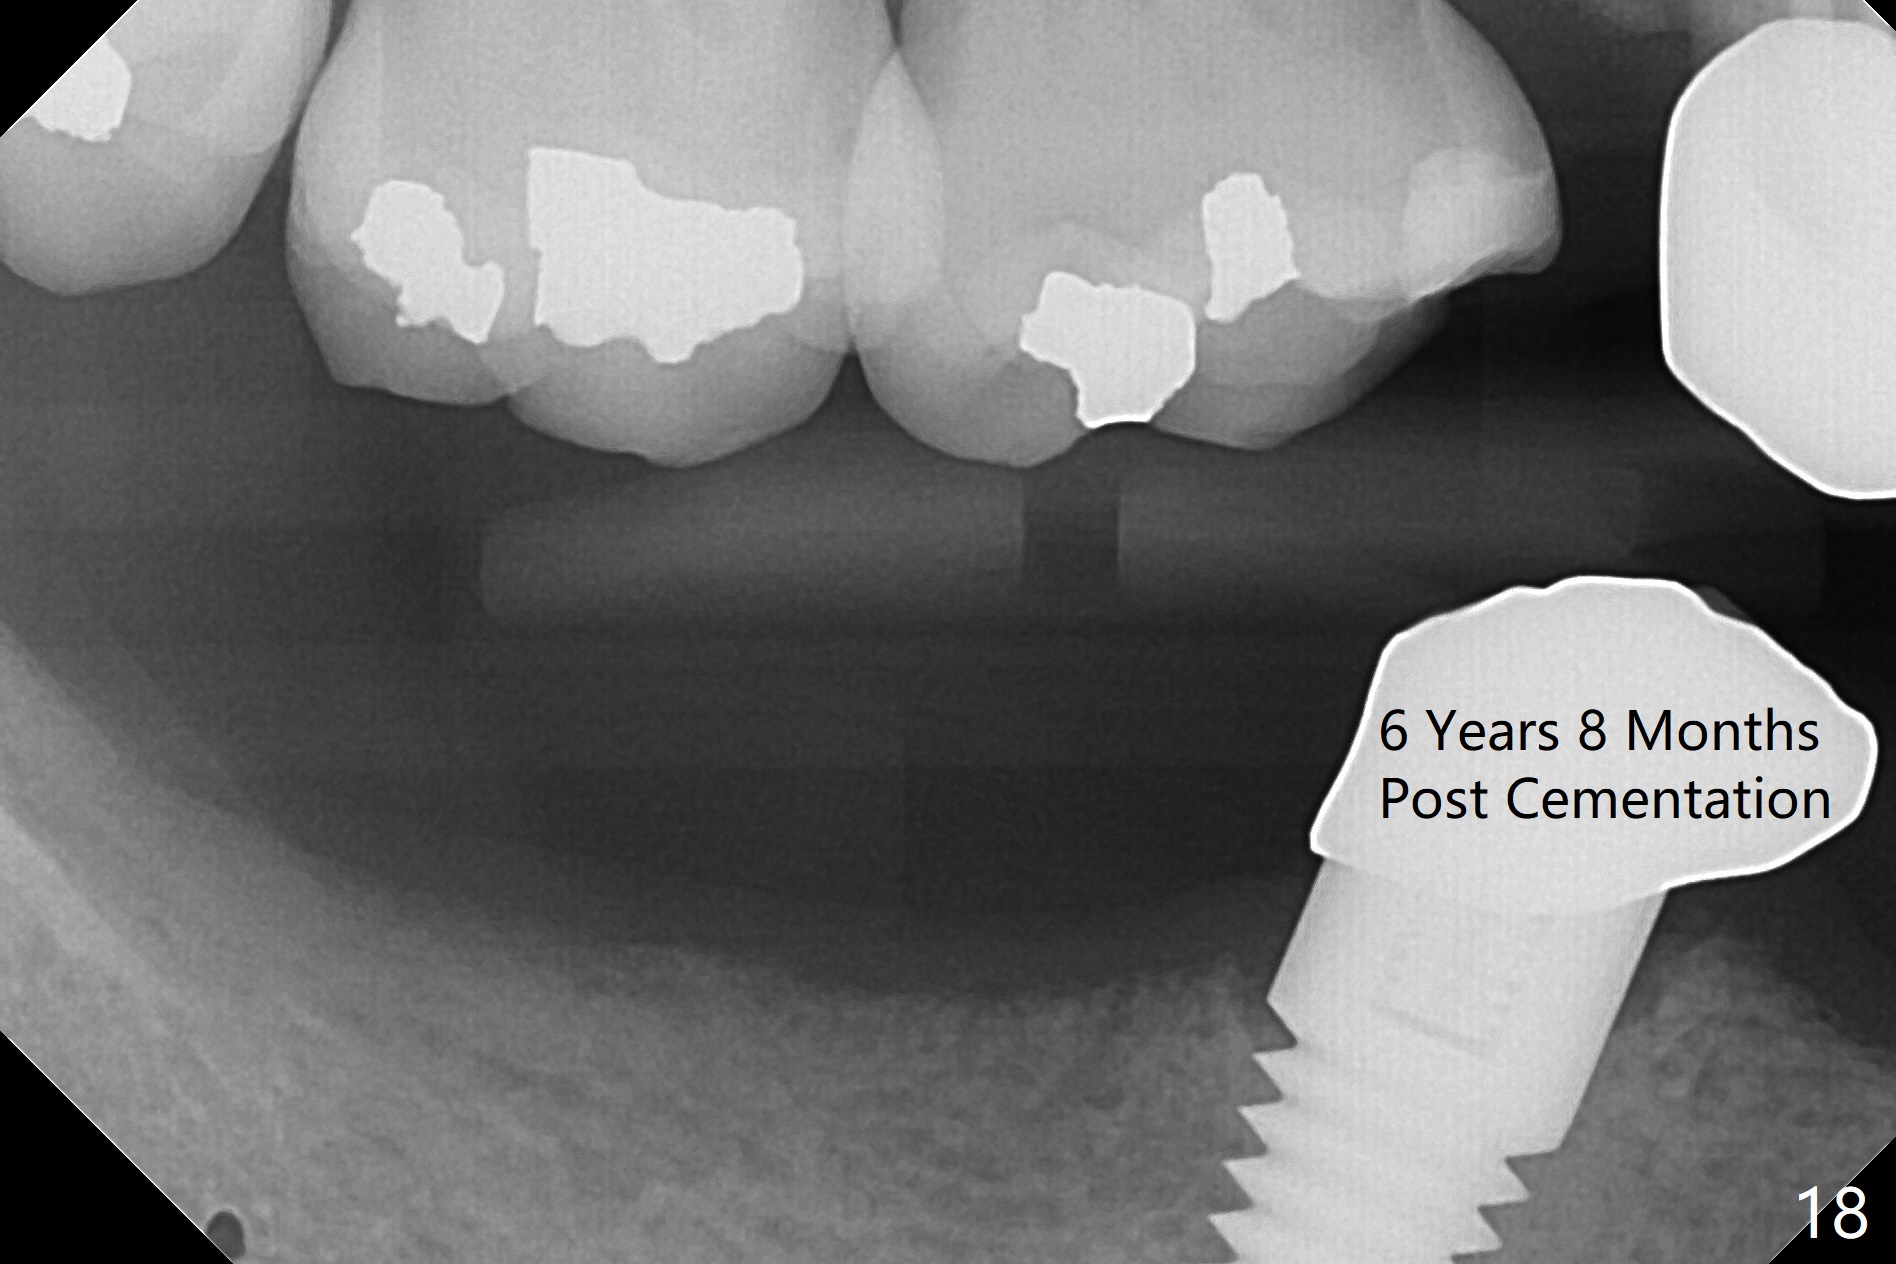

Panoramic X-ray taken 9 months post cementation shows the clearance from the Mental Loop (Fig.16). Although no drill technique is safe for the neurovascular bundle, the implant tends to deviate buccal, causing mental show through. It is still safe to make lingual osteotomy for a few millimeter and place a smaller implant (<4.5 mm). There is no bone loss 4 years 2 months post cementation (Fig.17) or 6 years 8 months post cementation (Fig.18).